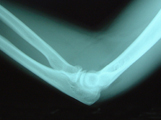

この写真は、整復後の写真です。傾斜した転移は十分に正常位置に整復されていることが確認されています。この写真は、8週目(58日目)のレントゲン写真です。骨折部位は治癒と判断されました。